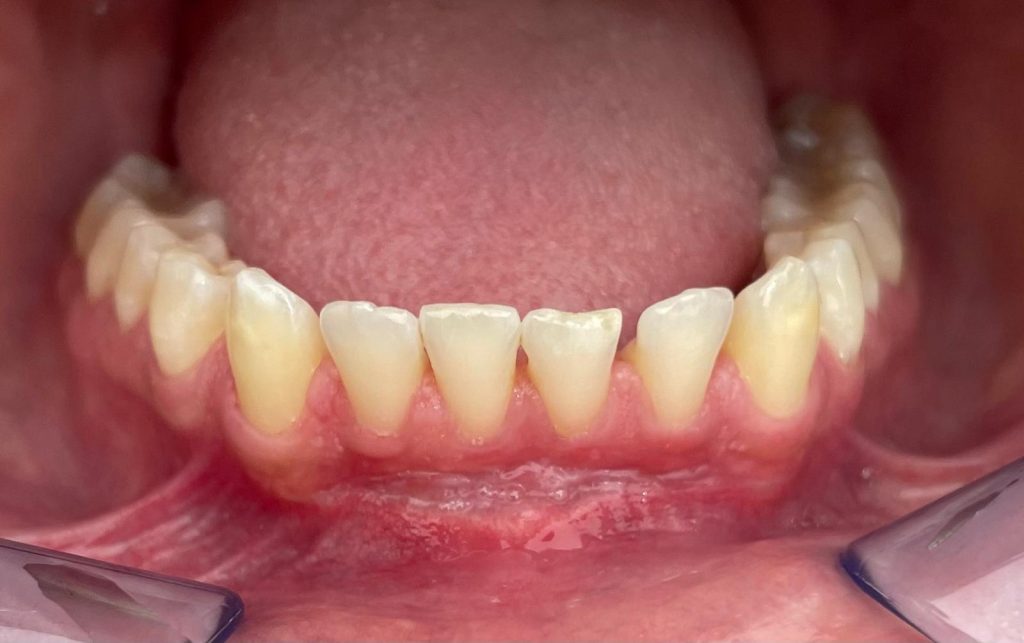

In questo caso è stata realizzata una copertura radicolare di un incisivo centrale inferiore innestando del tessuto connettivo prelevato dal...